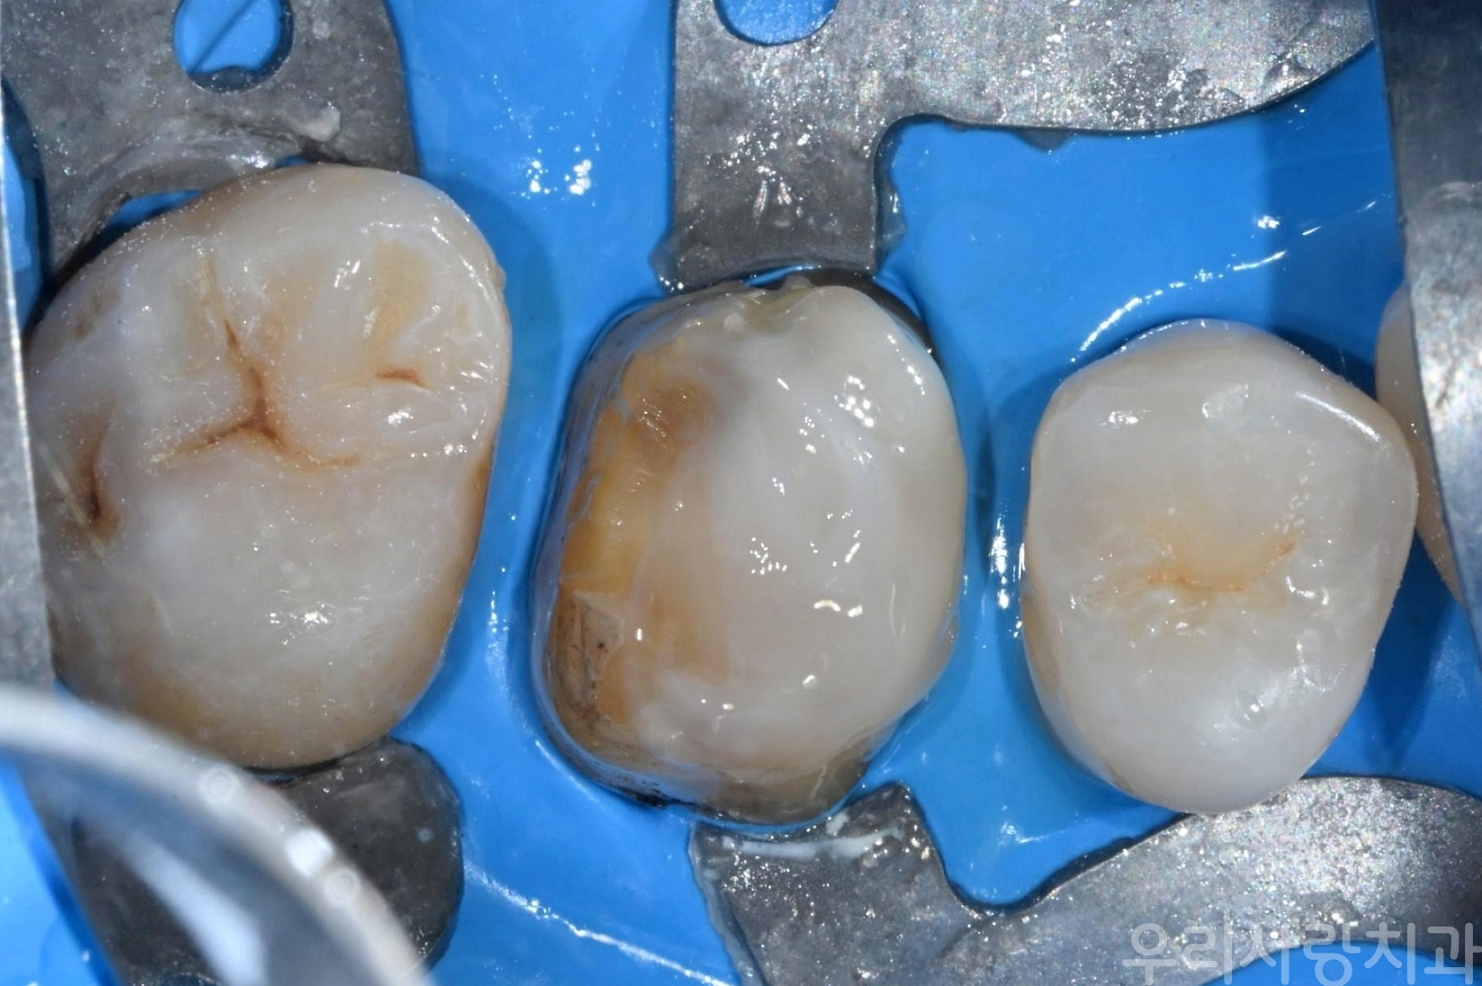

▲ 러버댐을 장착하여 침과 습기를 완벽히 차단한 상태

충치를 제거하고 나면 치아에 웅덩이처럼 파인 부분이 생깁니다. 이 부분을 단순히 본만 떠서 씌우는 것이 아니라, 단단한 레진(Resin) 재료를 이용해 꼼꼼하게 채워 넣어 치아를 보강합니다. 이를 통해 치아 내부를 완벽히 밀봉하고, 세균 침투를 막으며, 나중에 발생할 수 있는 시린 증상도 예방할 수 있습니다.

▲ 충치 제거 부위를 레진으로 밀봉하고 다듬은 모습 (레진 코어)